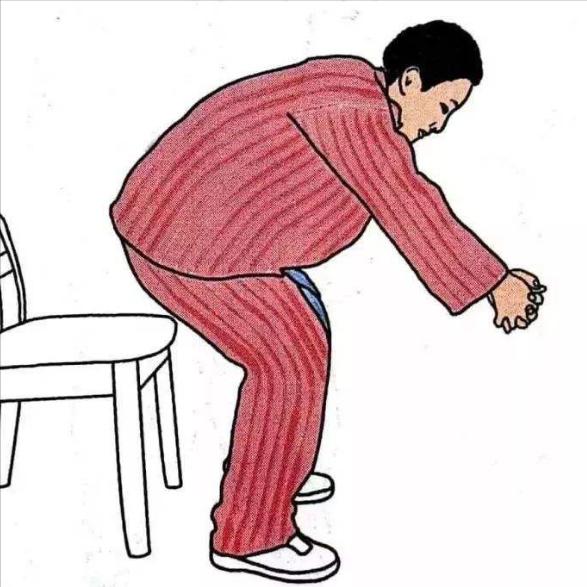

之前讲到影像学片子,膝盖和腰椎比较多,今天说些比较小众的——锁骨骨折,肘关节脱位,手部损伤等等👇🏻👇🏻【锁骨骨折的典型症状】01.疼痛与压痛——骨折部位出现持续性或阵发性剧烈疼痛。02.肿胀与皮下瘀斑——骨折后局部软组织损伤和出血,导致肿胀迅速出现,可能伴随皮下瘀血或青紫。03.畸形与异常活动——锁骨缩短、成角或旋转畸形,如骨折端上翘、隆起或凹陷。04. 活动受限——上肢抬举、伸展等功能受限,肩关节活动时疼痛加剧,甚至完全无法活动。05. 骨擦音/骨擦感——骨折断端摩擦时可触及异常活动或听到骨擦音,是骨折的典型体征。【肘关节脱位】01. 关节畸形——后脱位(最常见):尺骨鹰嘴向后突出,肘前窝饱满,前臂外观缩短,呈“靴状畸形”。——侧方脱位:肘关节向内或向外偏斜,形成肘内/外翻畸形。02. 肘后三角关系破坏 ——正常肘关节屈曲时,肱骨内/外上髁与尺骨鹰嘴构成等腰三角形;伸直时三点成一直线。——脱位后此关系完全失常。03. 弹性固定 ——关节被周围紧张韧带“锁扣”于半屈位,被动活动时有弹簧样阻力感。04. 骨性标志异常 ——后脱位时可触及肘后空虚感,尺骨鹰嘴异常隆起;——前脱位可触及肱骨远端。【手部骨折】拳击手骨折——握拳撞击——通常发生在第五掌骨(cr.骨科小龙笔记)大家如果还有关于骨折或者其他身体损伤的问题,都可以下方留言讨论